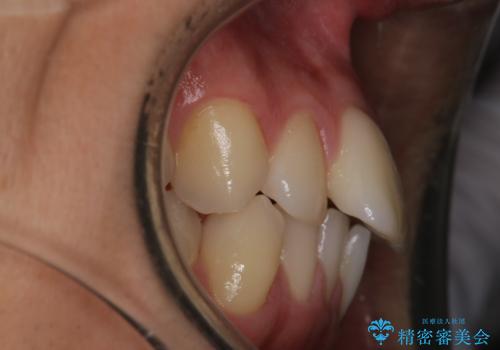

患者様よりシュミレーション通りに歯が動くか心配との事だったので

出来るだけ計画通りに歯を動かすために、マウスピース1枚あたりの使用時間を長めに使っていただきました。

そのため、多少治療期間が延びましたが、リファイメント(マウスピースの再発注)なしで終了することができました。